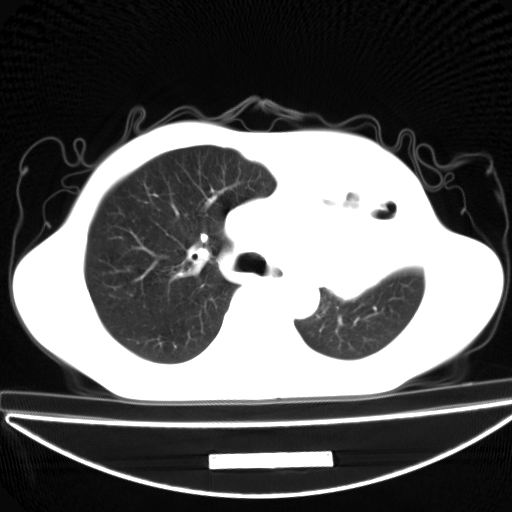

以下是引用杀毒软件在2009-4-28 17:58:00的发言:[br]考虑----左肺慢性肺脓肿形成继发上叶含气不良---抗炎后复查---待排肿瘤所致[br][br][本贴已被 杀毒软件 于 2009-4-28 18:01:26 修改过]